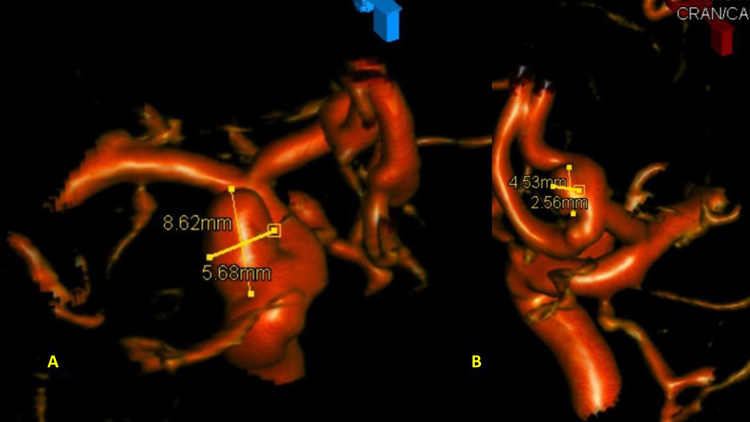

After careful measurements of the parent vessels, aneurysm sac, and aneurysm neck, we decided to proceed with Primary Coil Embolization of the Acom Aneurysm first, followed by the Right ICA Aneurysm next. Despite greater suspicion in the Acom region, a significant level of uncertainty remained, and we felt it was better to secure both aneurysms if capable of being performed safely. (Figure 4.)